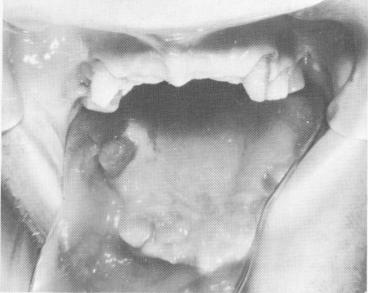

A 52-year-old man with an extremely powerful bite had broken a few of the anterior maxillary teeth off his removable partial denture (Fig. 10-188). His remaining teeth showed rampant caries (Fig. 10-189).

Fig. 10-189. The poor condition of the remaining teeth is clearly evident.